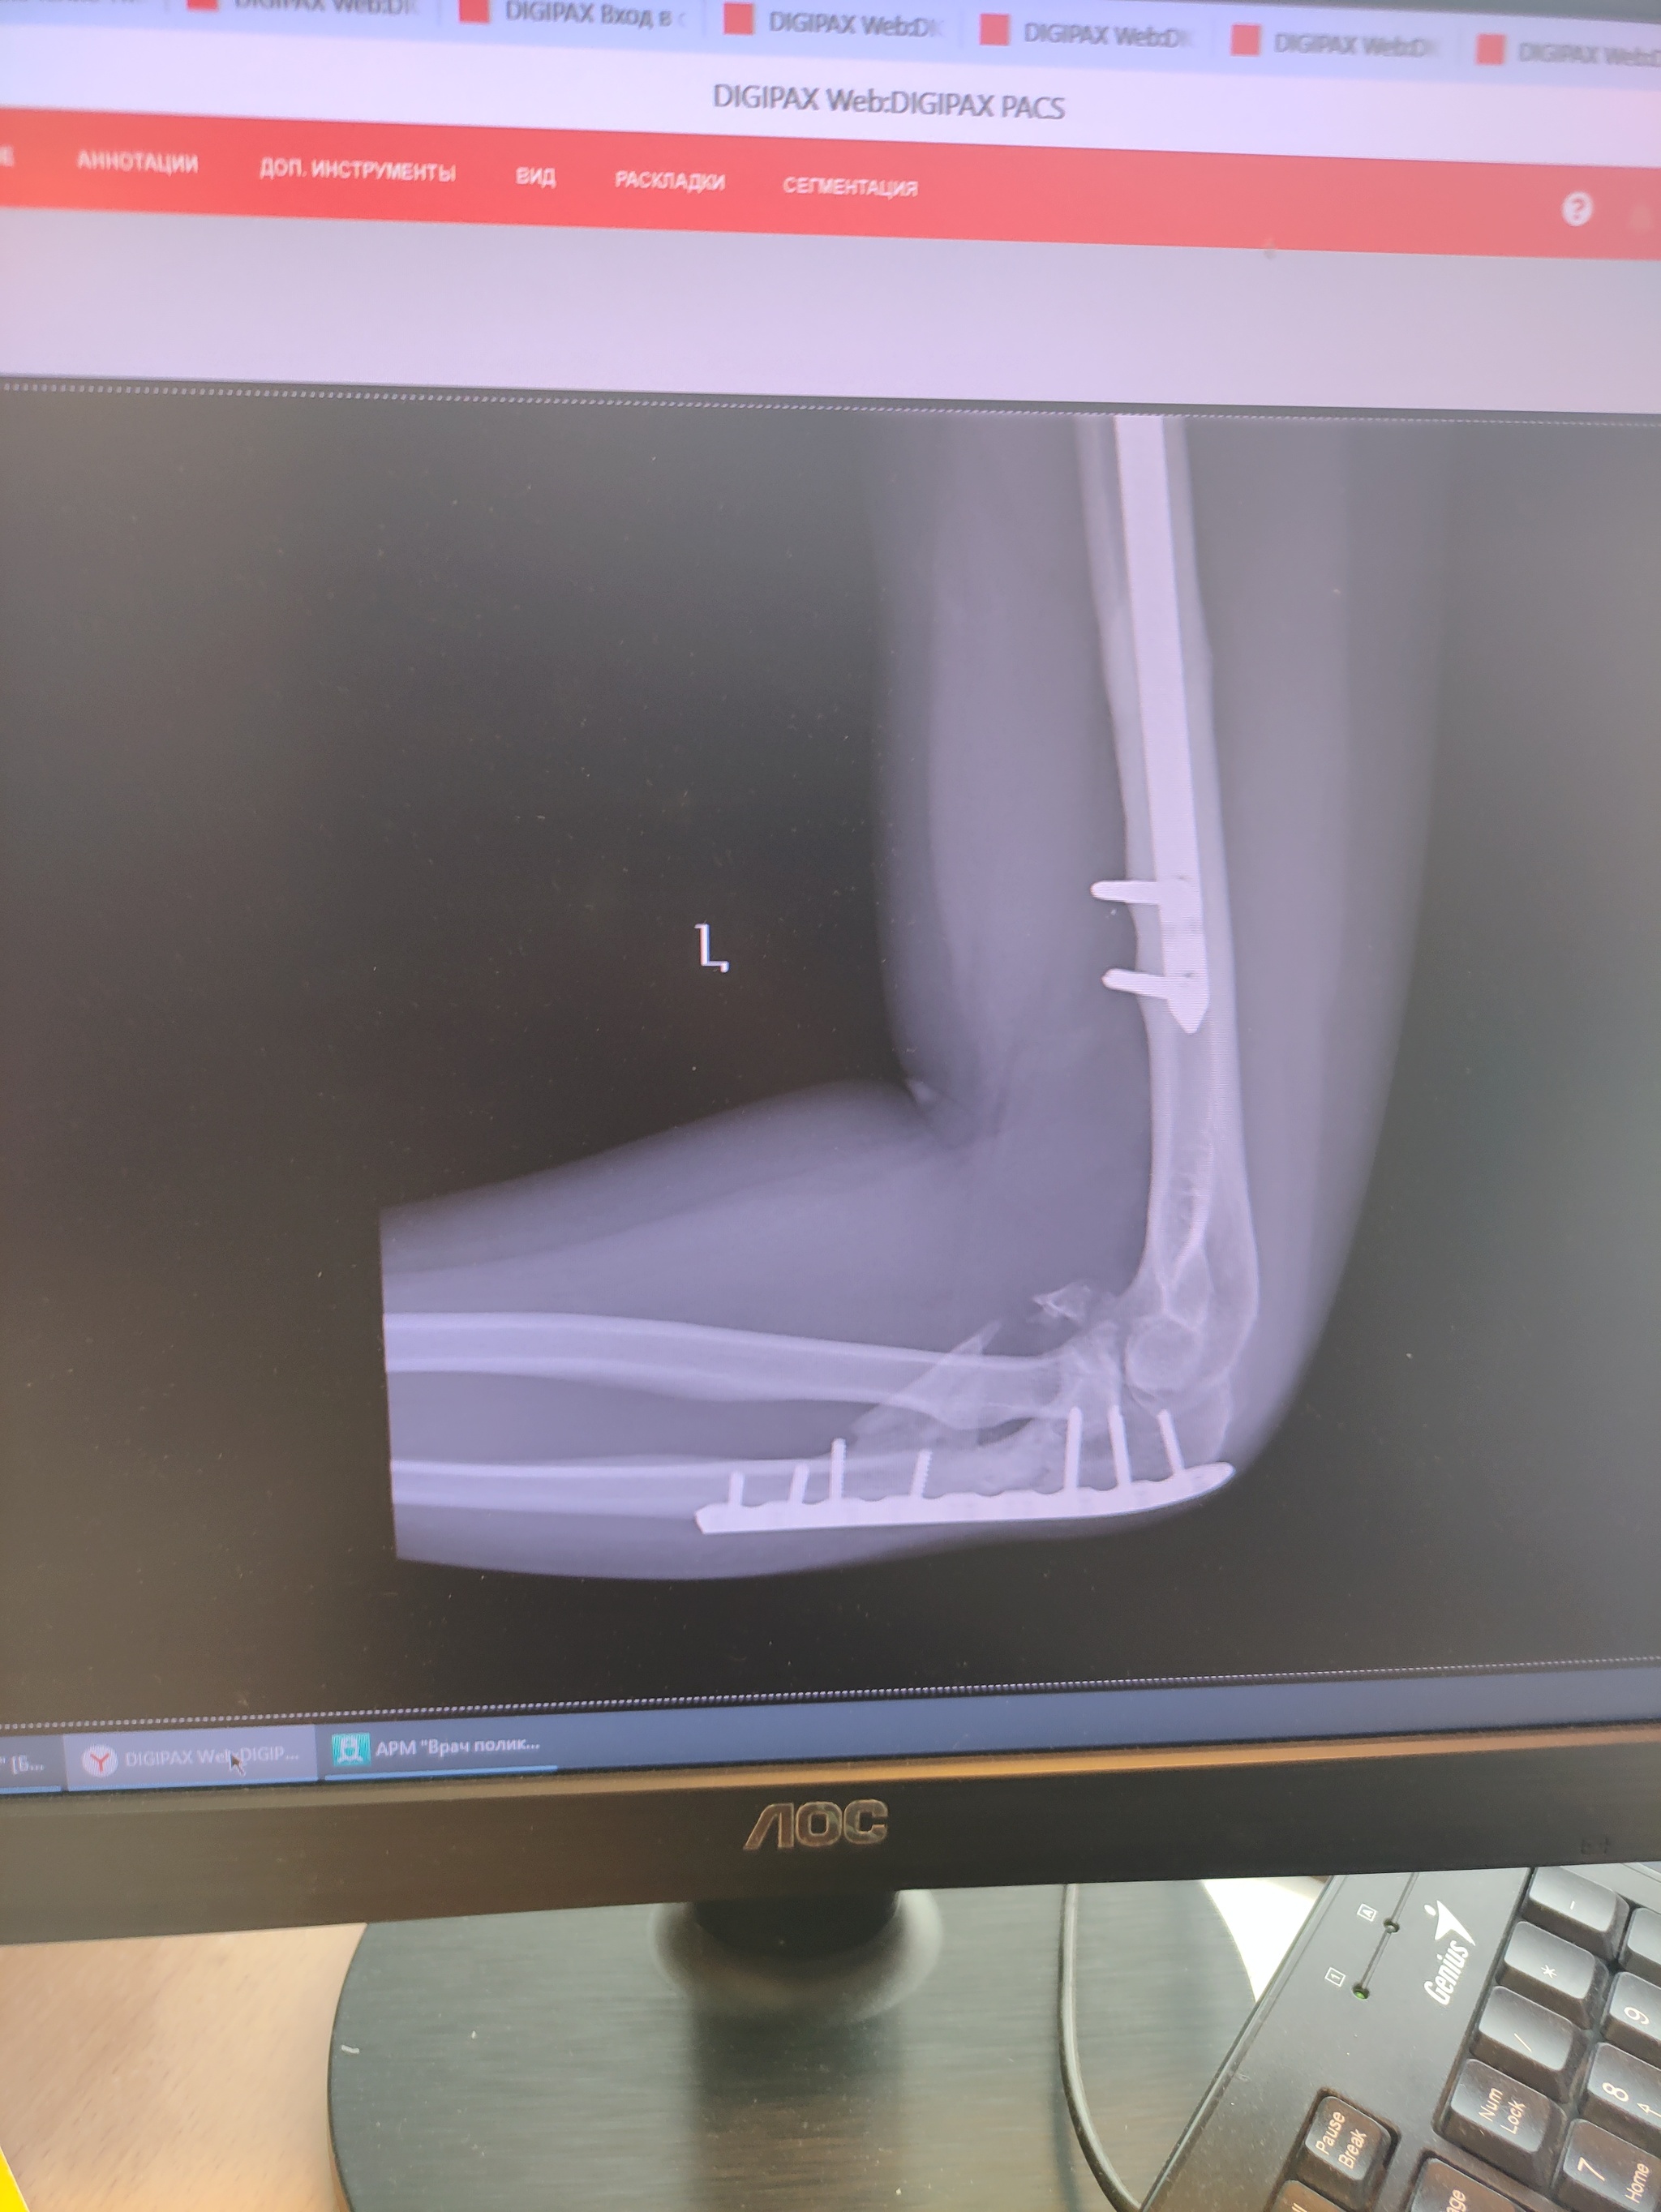

Устройство руки представляете себе? Есть плечевая кость, есть локтевой сустав, в него входят две кости - локтевая и лучевая. Я сломал обе. Локтевой сустав цел, но окончания лучевой и локтевой кости - в щепки. Просто в много мелких острых щепок. Вместо предплечья теперь - бесполезный окорок, который висит только на сухожилиях. Называл его ласково - "моя рулька".

Короче, две кости соединили железкой и вставили в сустав. Одну головку кости (видимо лучевой) выкинули нахрен, собаки были довольны.

Хирург сразу предупредил, что подвижности руки, такой как прежде, уже не будет никогда. Так оно и стало.